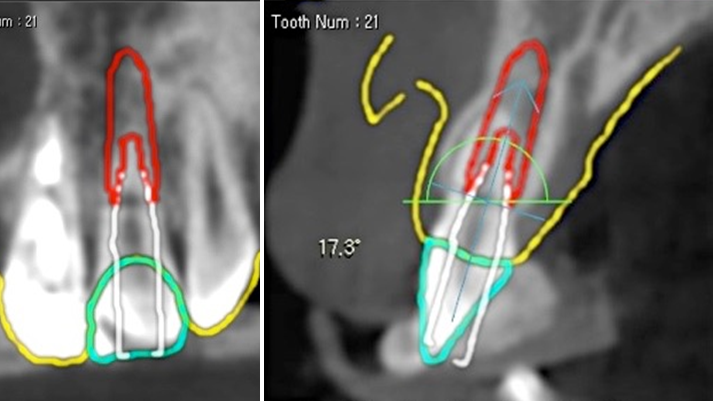

Clinical case: Extraction, immediate placement & loading using

R2GATE solution in aesthetic zone

- Courtesy of Dr. Jong-Cheol Kim, Korea-